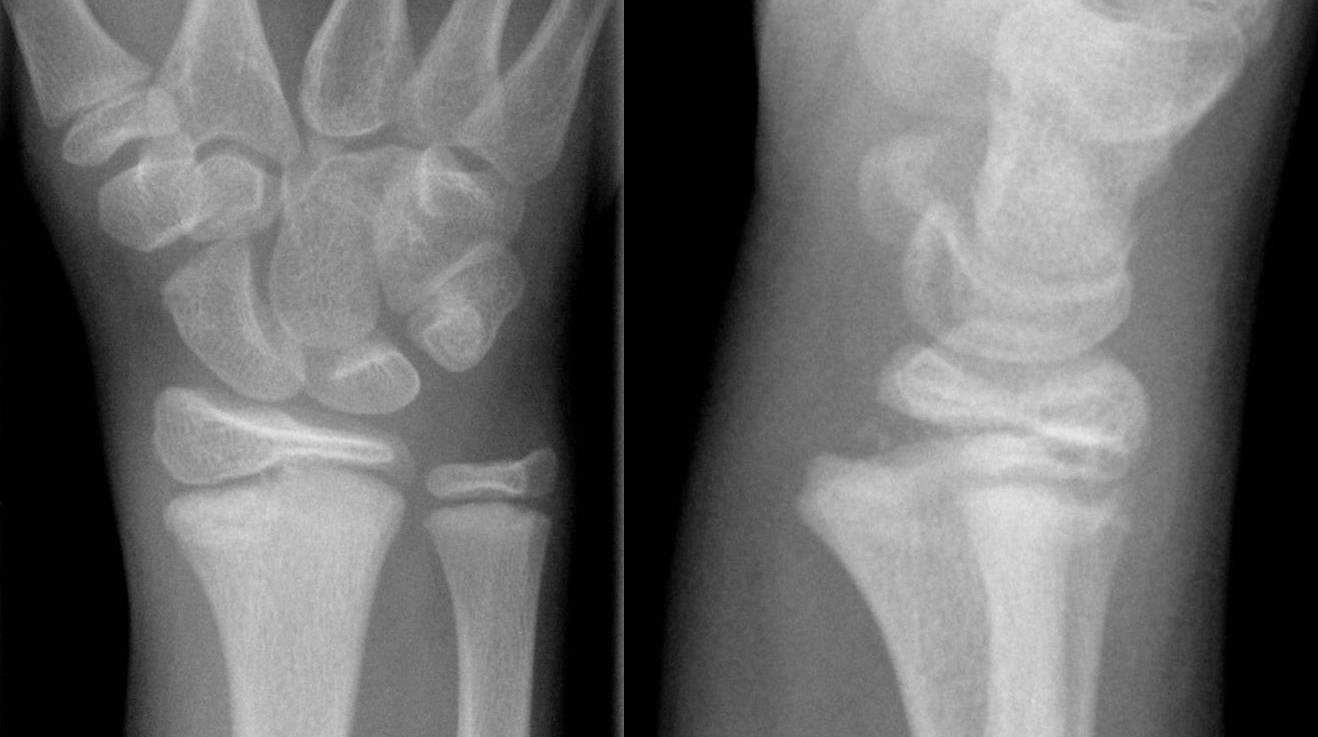

Distal radiusfraktur (handled)

Distal radiusfraktur är den vanligaste frakturen överhuvudtaget. Drabbar oftast kvinnor med osteoporotiskt skelett (fallskada inomhus eller utomhus vid halka). Högenergiskador i samband med trafikolyckor och sport drabbar vanligen yngre individer.

Olika distala radiusfrakturer

- Dorsal felställning: Colles fraktur

- Volar felställning: Smiths fraktur

- Volar felställning med intraartikulärt engagemang: Smith-Barton fraktur

Behandlingen bör individualiseras och bygga på klassificering av frakturen i olika svårighetsgrader.

Smith fraktur och Smith-Barton fraktur är ofta instabila och kräver rigid fixation, Smith-Barton oftast med volart anbringad frakturplatta. Colles fraktur kan ibland behandlas enklare, exempelvis med dorsal gipsskena. Denna fraktur dislocerar dorsalt, men även med axial kompression av radius. Graden av radiusförkortning anses påverka slutresultatet och kraftig förkortning bör därför reponeras.

Behandlingen kan utgå från ett klassificeringssystem, exempelvis Older som delar in frakturer i 4 typer beroende på initial felställning.

- Typ 1: liten felställning, radiusförkortning < 2 mm

- Typ 2: mer uttalad felställning, radiusförkortning 2-5 mm

- Typ 3: uttalad felställning med komminut fraktur av dorsala cortex, radiusförkortning > 5mm

- Typ 4: intraartikulär komminut fraktur med kraftig felställning.

Operationsindikation föreligger (om vital patient)

- Ulna+ 2-3 mm

- Dorsalbockning > 20° (mätt från normal/ursprungsläget)

- Hak i ledytan > 1-2 mm

Operation sker med volar platta.